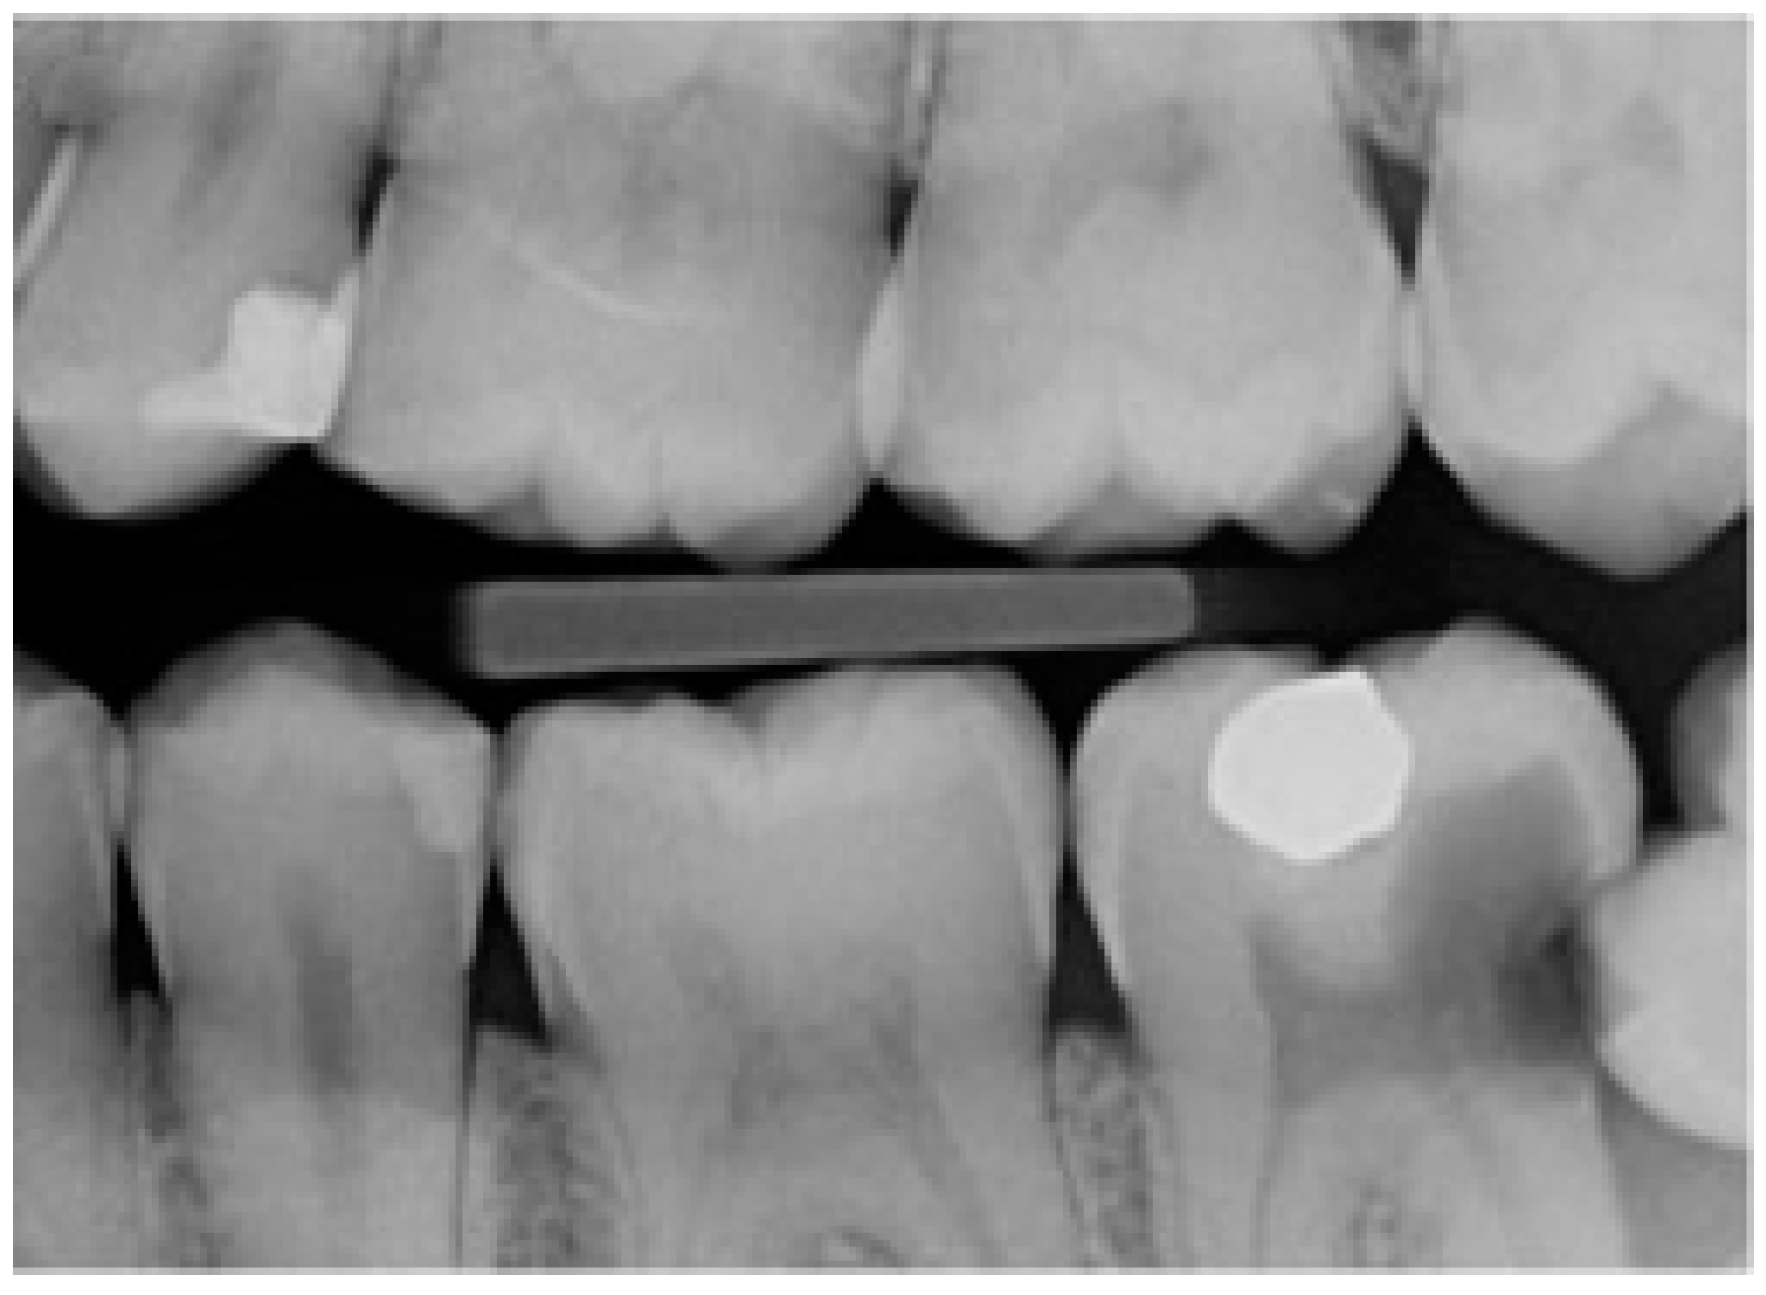

In this study, partial emergence or partial eruption of the mandibular third molar was determined by assessing the position of the third molar in relation to that of the adjacent mandibular second molar. Figure 1 illustrates a partially erupted mandibular and impacted third molar as seen on a bitewing radiograph, while Figure 2 illustrates a panoramic tomograph of a mandibular third molar that was deemed to be partially erupted. We judged the partial eruption of the third molar from the cusp levels; the third molars were deemed to be partially emerged when one of the cusps was positioned above the occlusal plane level or above the external oblique ridge. In cases in which these anatomical landmarks were not visible on the radiograph, the cementoenamel junction (CEJ) of the adjacent second molar in relation to the position of the marginal ridge of the adjacent mandibular third molar was used to obtain information on the depth of the third molar and was used to judge its eruption status [12]. This assessment method is a modification of the original Pell and Gregory classification [13]. Classes IIIA, IB, IIB and IIIB of the original Pell and Gregory categorization were included, thus excluding fully erupted potentially functional and fully impacted third molars. This classification (Figure 3) was applied to all third molar impaction types such as mesial, horizontal, distal, vertical and transverse.

Figure 2. Right panoramic tomograph indicating the various anatomical landmarks required for the assessment of mandibular third molar partial eruption/emergence.